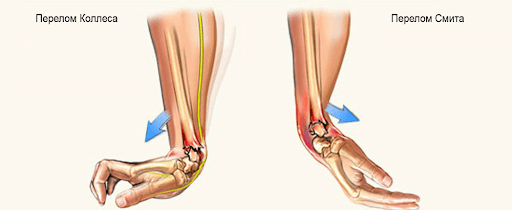

Переломы кисти диагностируют у 30% пациентов, которые обращаются к травматологу. Распространенность травмы объясняется тем, что при угрозе падения человек автоматически выставляет руки перед собой, что приводит к тяжелым повреждениям. Перелом костей кисти имеет выраженную клиническую картину, но для уточнения диагноза необходимо сделать рентген.

Перелом кисти - открытая или закрытая травма, при которой наблюдается полное либо частичное повреждение костных составляющих. Чаще всего оно связано с внешним механическим воздействием на кисть. Это может быть падение груза, удар тяжелым предметом, падение с упором на кисть, зажатие ладони между твердыми поверхностями.

Если разрушена середина кости, такой перелом называют диафизарным, при травмировании головки кости - эпифизарным. При переломе костей внутрь сустава диагностируют перелом Беннета или Роландо, это внутрисуставная травма. Если линия разлома не затрагивает сочленение, это внесуставный перелом.